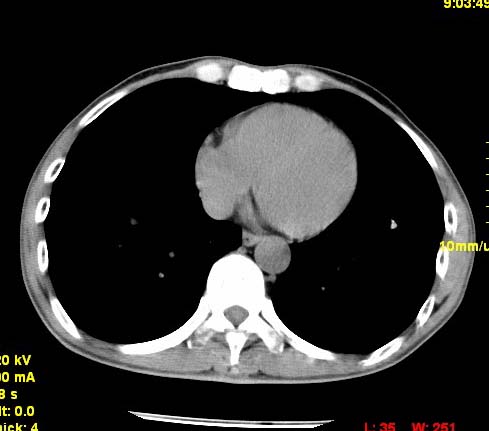

以下是引用wangzhengyuan在2007-11-11 23:31:00的发言:[br]钙化灶,看上去不像转移。

以下是引用zjzjr在2007-11-12 8:35:00的发言:[br]考虑错构瘤,建议定期复查.

以下是引用卜一在2007-11-12 5:59:00的发言:[br]病灶本身不像转移,不知有没有以前的胸部ct片,若有,则可以对比以下,若是新出现病灶,应高度警惕“转移”的可能![br]